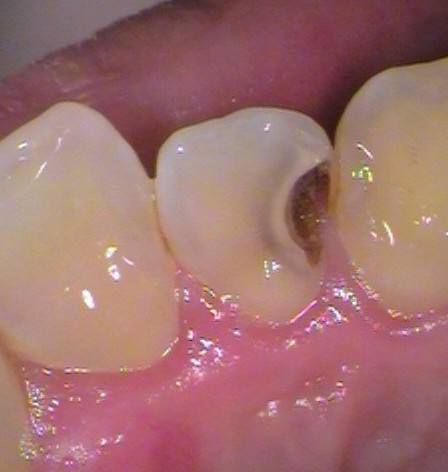

After

銀歯の中以外にも、別の箇所からの虫歯。セラミックで治療。